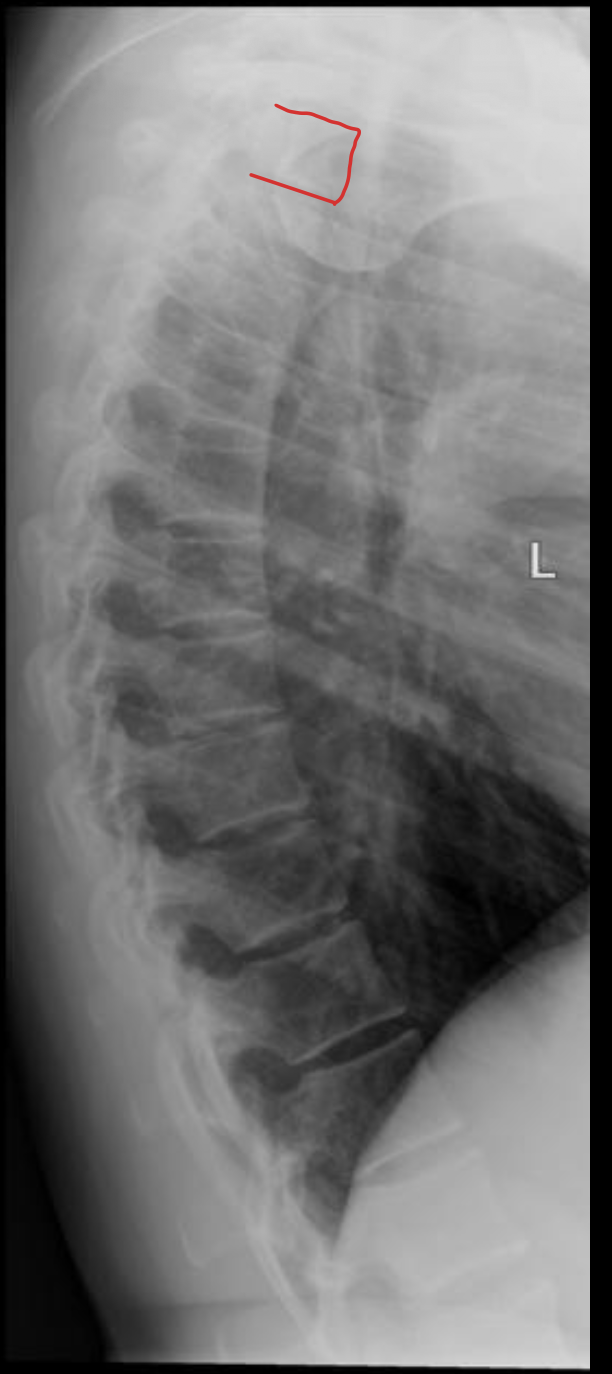

胸椎

THORACIC

T1

T2

T3

T4

T5

T6

T7

T8

T9